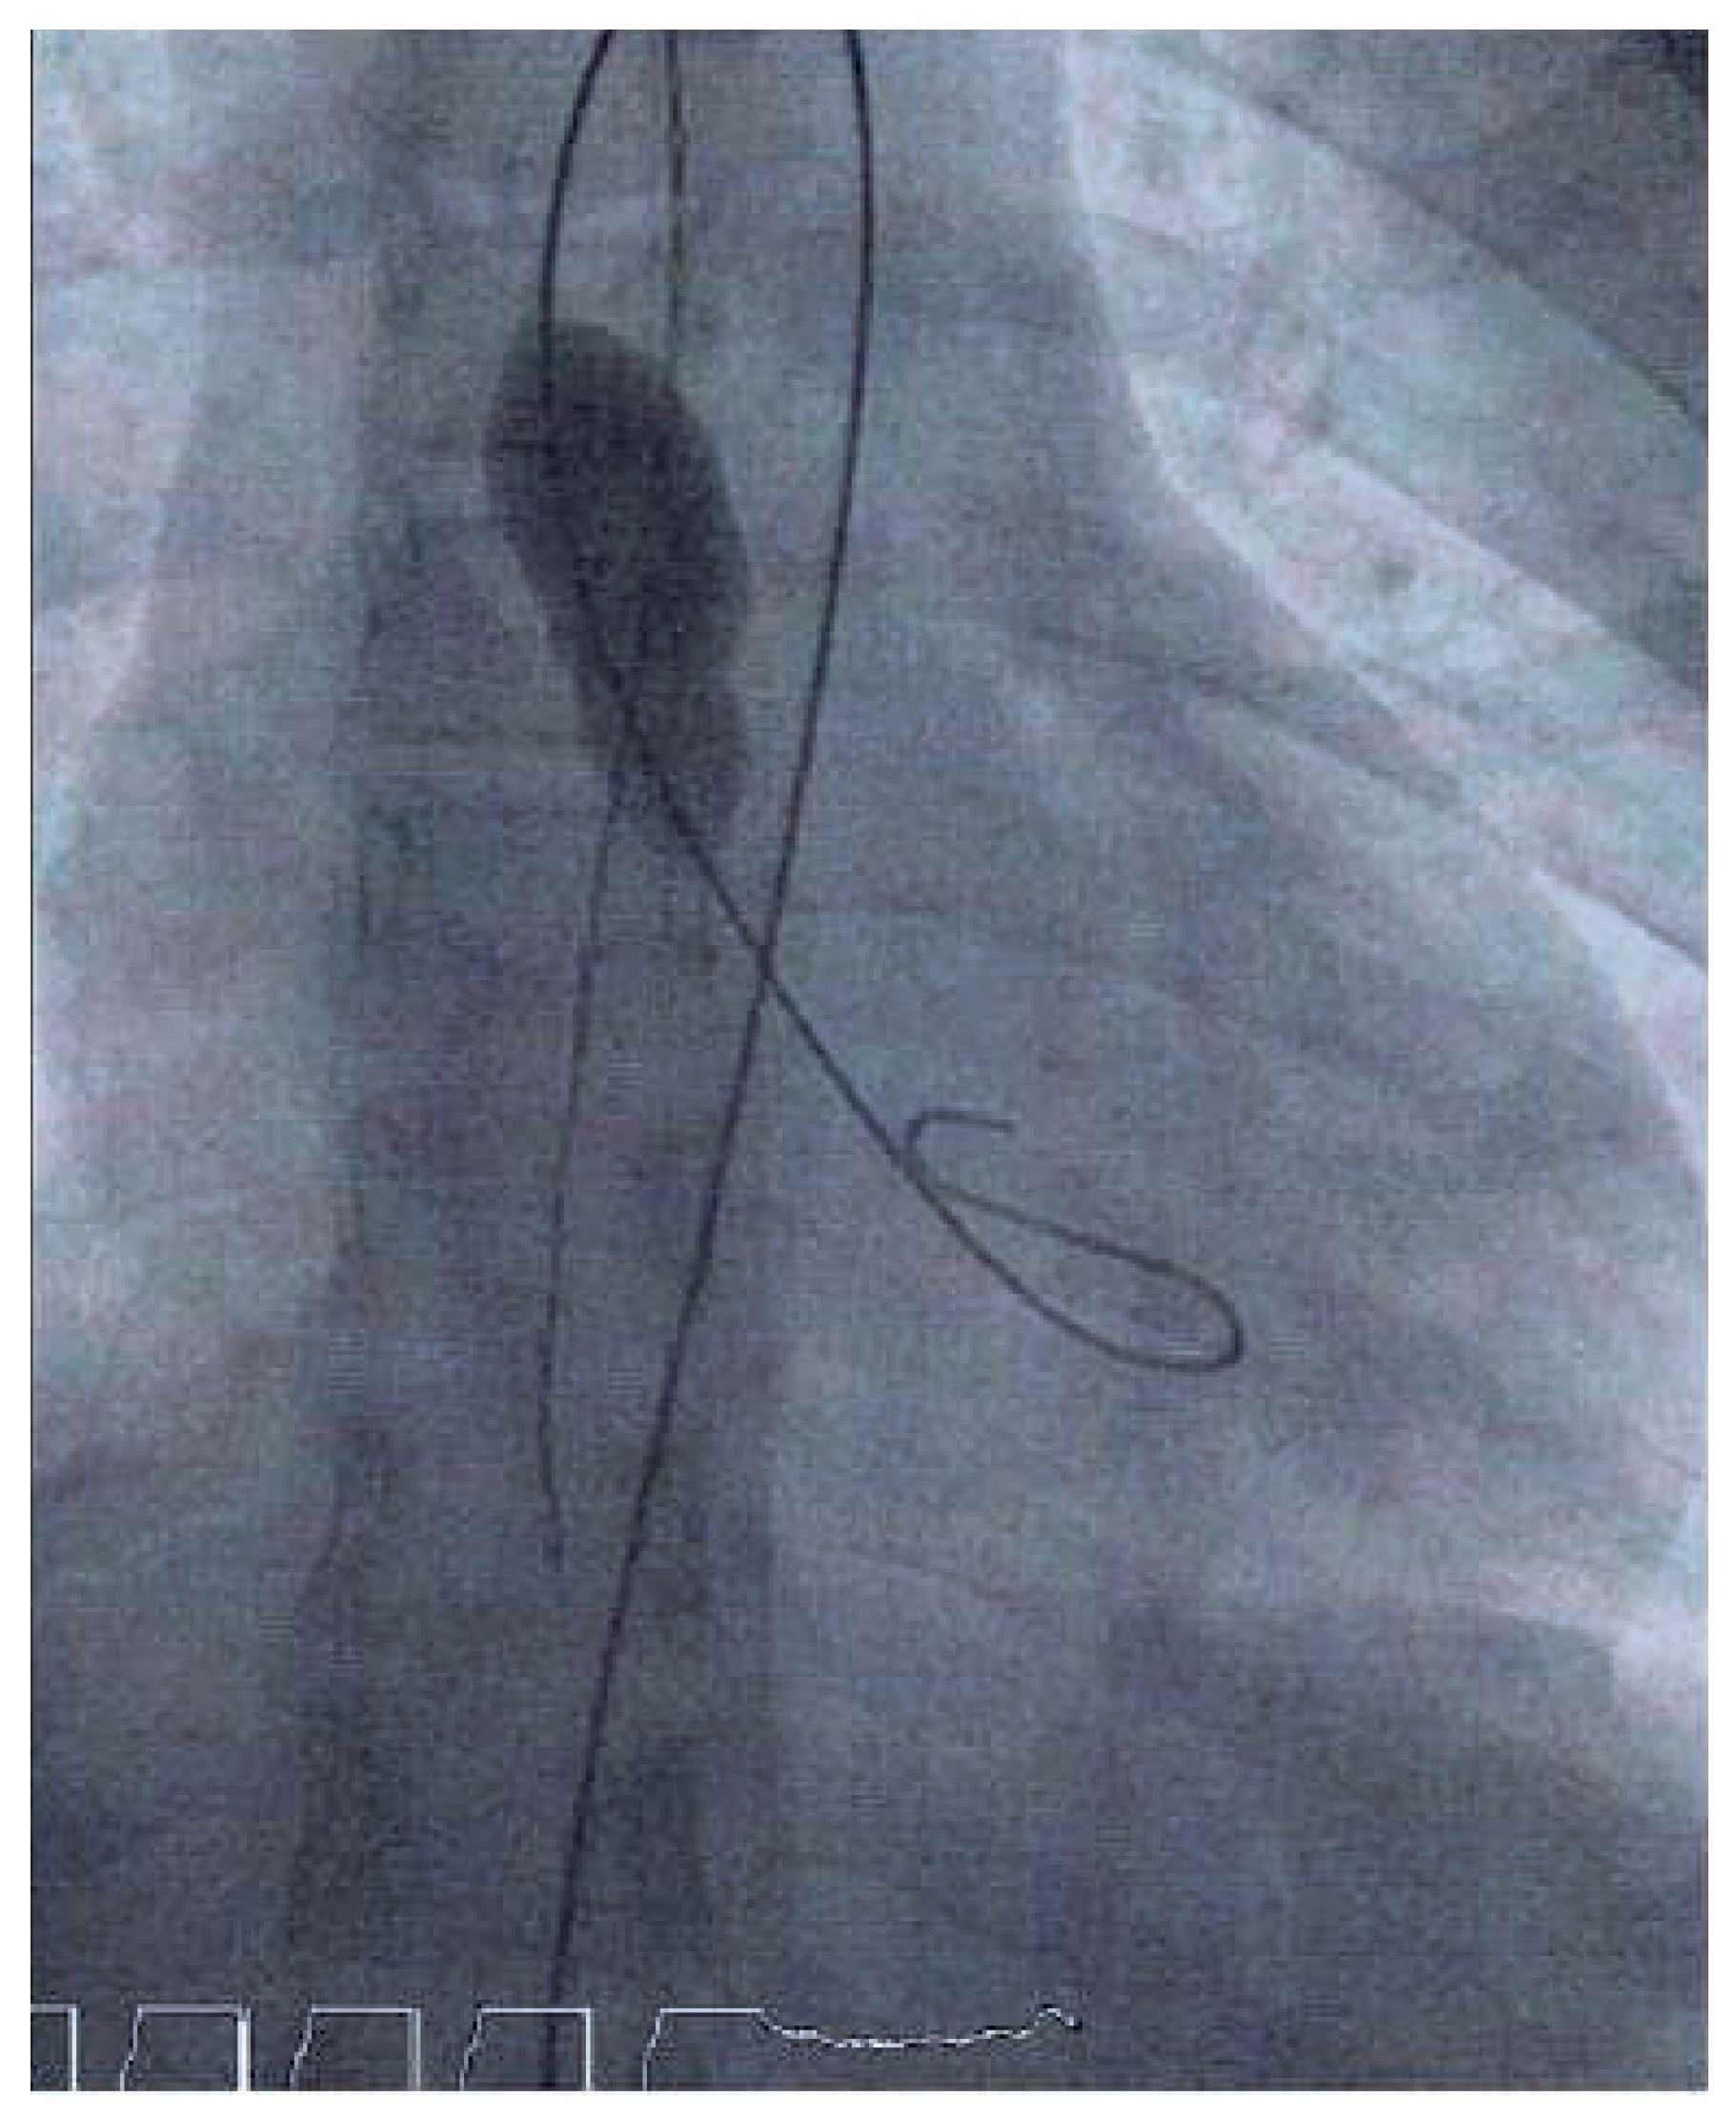

Prolonged Complete AV Block After Balloon Aortic Valvuloplasty in a Child

Case report